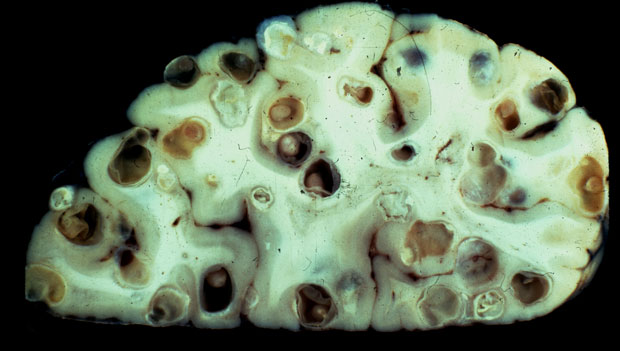

inclusive no Recife. Por mês, o principal serviço de referência, o Hospital das

Clínicas da Universidade Federal de Pernambuco admite oito novos doentes

crônicos, com a forma grave da doença parasitária, etapa na qual o verme já

provocou estragos quase irreparáveis, dilatando vasos do esôfago, matando por

hemorragia digestiva. No Hospital da Restauração, também chegam crianças e

adultos com lesões no sistema nervoso. E no Pronto-Socorro Cardiológico de

Pernambuco (Procape) chama a atenção à hipertensão pulmonar pela esquistossomose.

Não há só amarelos e com barriga d’água. A esquistossomose ganhou outras

feições.

A suspeita confirmou-se no Hospital das Clínicas da Universidade Federal de

Pernambuco, onde passou quase dois meses internado. Evandro tomava banho no Rio

Sirinhaém e não sabia do risco de contrair a doença. "Só agora sei que o

verme se aloja no caramujo e dele passa pra gente. Depois de muita fisioterapia

consegui sair da cama", conta. As lesões neurológicas são raras, mas numa

região endêmica tornam-se mais comuns, explica a médica Ana Lúcia Coutinho, do

Hospital das Clínicas, que se dedica à esquistossomose como fez seu pai,

Amaury Coutinho. Por mês, indigna-se a médica, são oito novos casos crônicos

admitidos no ambulatório de gastroenterologia da unidade de saúde, depois de

uma hemorragia ou de outra complicação séria, descobrindo só assim a condição

de portador. No início do século passado, a situação era pior. O diagnóstico da

esquistossomose era dado após a morte do paciente, segundo registros da cadeira

de anatomia patológica da Faculdade de Medicina do Recife, assinados por outro

Coutinho, Aluízio Bezerra, primo de Amaury.